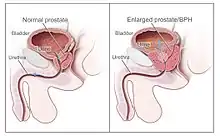

Prostate Cancer

Prostate cancer is the second cause of cancer and the most common malignancy associated with deaths in men worldwide.[66] Current methods of treatments are invasive resection therapy, radiation therapy, and prostatectomy that can cause complications such as incontinence, impotence, and damage to surrounding organs and tissues.[67][17] Current studies have shown success in using SDT as a stand-alone treatment.[68] SDT uses mitochondria related apoptosis for the reduction of cell viability. SDT for prostate cancer treatment has also been used alongside chemotherapeutics such as docetaxel microbubbles.[17][67][68] This has shown to enhance the effects of docetaxel through a reduction in tumor perfusion and enhanced necrosis and apoptosis.[68] The SDT and docetaxel group showed reduction in tumor growth.[68] Overall, the use of SDT has shown promising results in prostate cancer treatment.